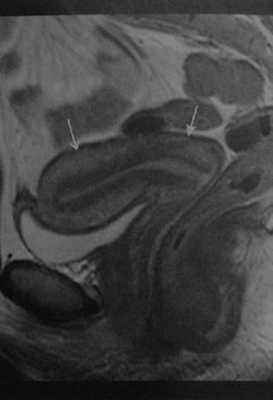

Нормальная матка у женщины 34 лет в первой фазе менструального цикла. Сагиттальная Т2-взвешенная МРТ. Зональная анатомия матки: наружный слой миометрия с промежуточной интенсивностью сигнала (стрелка с открытым наконечником), гипоинтенсивный внутренний слой миометрия (зона соединения) и гиперинтенсивный эндометрий. Шейка матки (стрелка): умеренно или незначительно гиперинтенсивная строма, гиперинтенсивная слизистая оболочка и слизь в просвете цервикального канала.